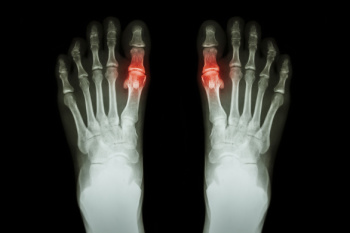

Gout – is caused by an excess of uric acid in the body. Common symptoms include pain, inflammation, and redness at the metatarsal/phalangeal joint of the base big toe. Gout can be treated by NSAIDs to relieve pain and inflammation, and other drugs that lower the acid levels in the body.

Gout is a form of arthritis that causes sudden and severe pain, often affecting the joints, particularly the big toe joint. The condition occurs when excess uric acid builds up in the body, forming crystals in the joints. The most common sign of gout is intense pain, typically starting in the middle of the night, along with swelling and redness in the affected area. The joint may become warm to the touch and feel tender, making movement difficult. In some cases, gout attacks can recur, leading to joint damage over time. Elevated uric acid levels in the blood can result from factors such as diet, dehydration, obesity, or kidney problems. Excessive consumption of purine-rich foods like red meat, seafood, or alcohol can trigger or worsen gout attacks. If you have had one or more gout attacks, it is suggested that you are under the care of a podiatrist who can offer you effective relief and management tips.

Gout is a form of arthritis that is characterized by sudden, severe attacks of pain, redness, and tenderness in the joints. The condition usually affects the joint at the base of the big toe. A gout attack can occur at any random time, such as the middle of the night while you are asleep.